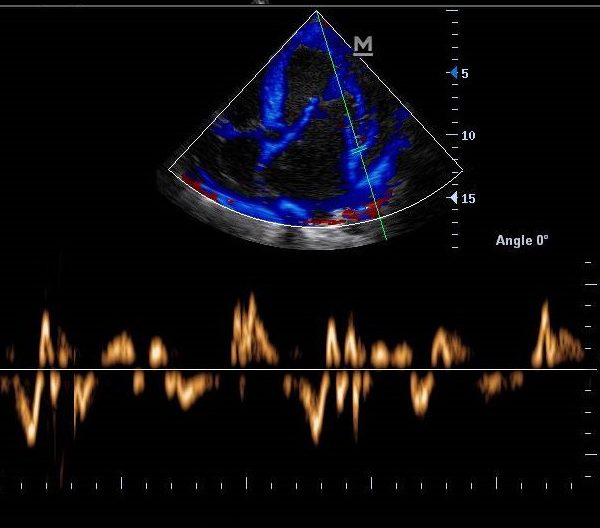

Choroby serca